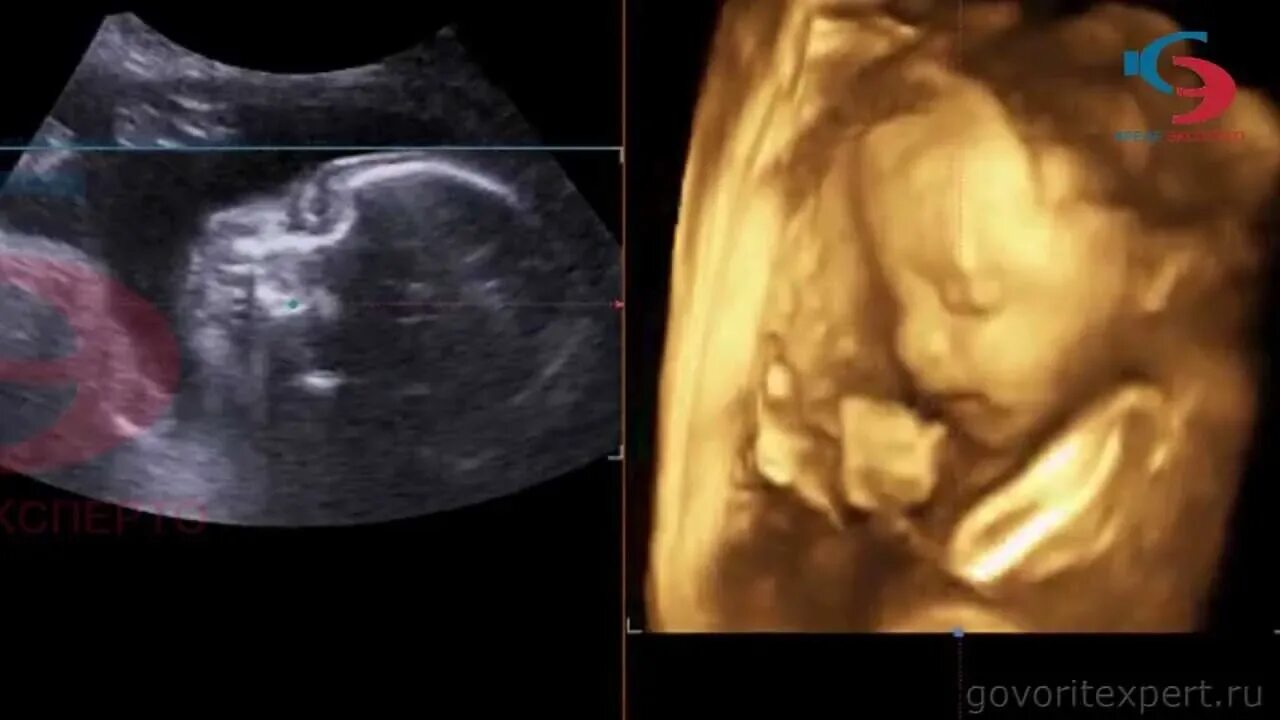

Через 20 недель